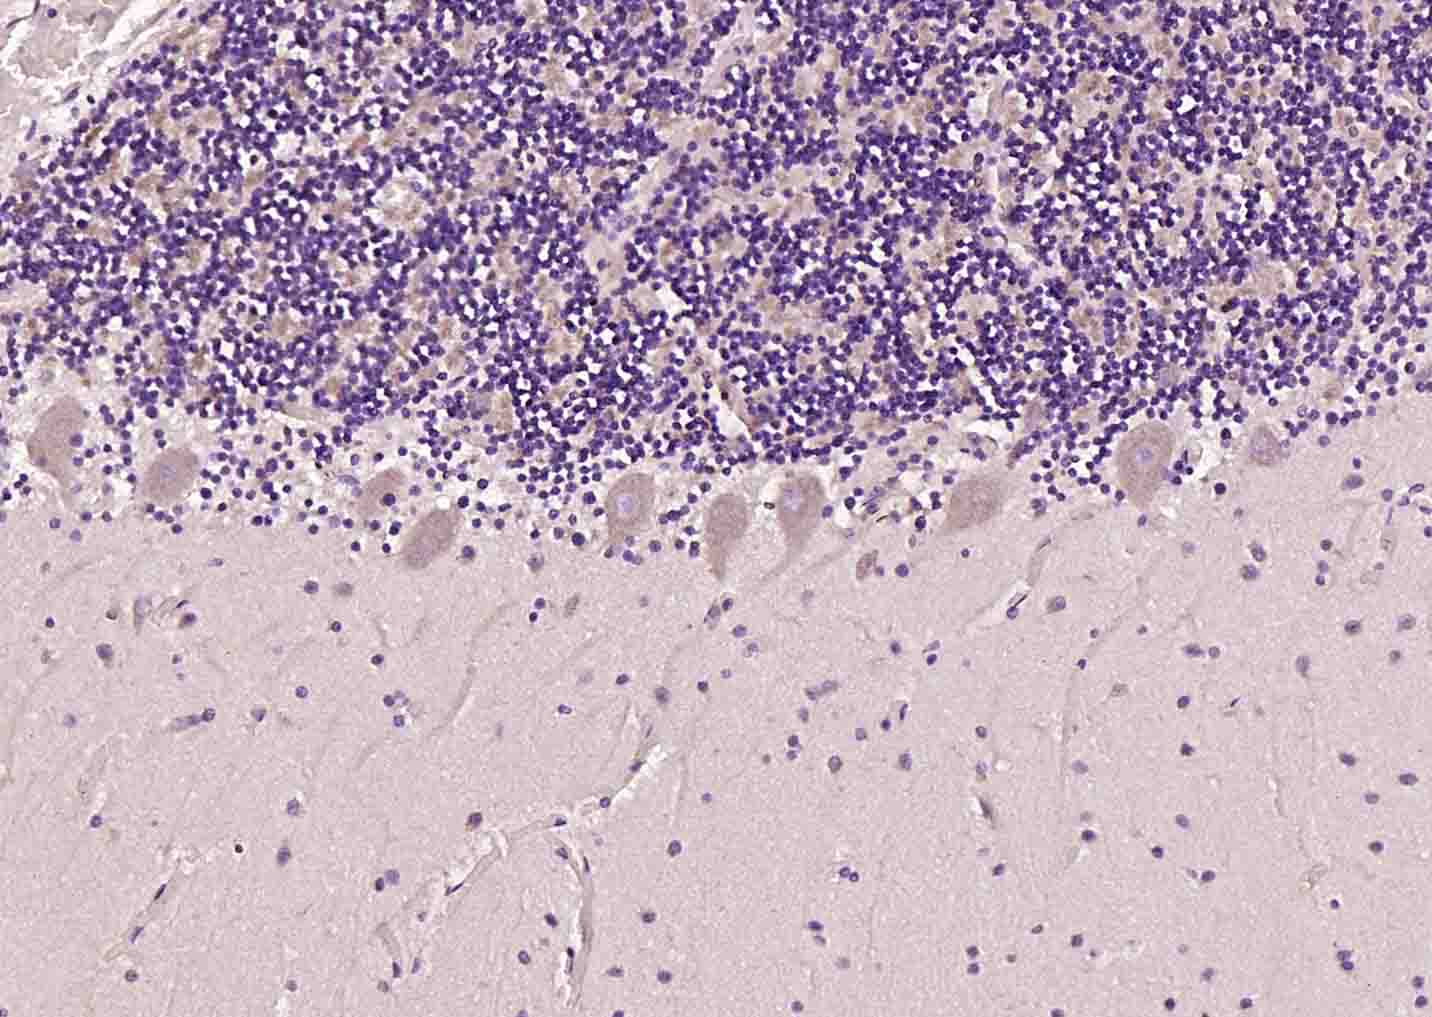

Paraformaldehyde-fixed, paraffin embedded (human cerebellum); Antigen retrieval by boiling in sodium citrate buffer (pH6.0) for 15min; Block endogenous peroxidase by 3% hydrogen peroxide for 20 minutes; Blocking buffer (normal goat serum) at 37°C for 30min; Incubation with (mu Opioid receptor) Polyclonal Antibody, Unconjugated (bs-3623R) at 1:200 overnight at 4°C, followed by operating according to SP Kit(Rabbit) (sp-0023) instructionsand DAB staining.

Paraformaldehyde-fixed, paraffin embedded (Rat brain); Antigen retrieval by boiling in sodium citrate buffer (pH6.0) for 15min; Block endogenous peroxidase by 3% hydrogen peroxide for 20 minutes; Blocking buffer (normal goat serum) at 37°C for 30min; Antibody incubation with (mu Opioid receptor) Polyclonal Antibody, Unconjugated (bs-3623R) at 1:400 overnight at 4°C, followed by operating according to SP Kit(Rabbit) (sp-0023) instructions and DAB staining.

Paraformaldehyde-fixed, paraffin embedded (Mouse brain); Antigen retrieval by boiling in sodium citrate buffer (pH6.0) for 15min; Block endogenous peroxidase by 3% hydrogen peroxide for 20 minutes; Blocking buffer (normal goat serum) at 37°C for 30min; Antibody incubation with (mu Opioid receptor) Polyclonal Antibody, Unconjugated (bs-3623R) at 1:400 overnight at 4°C, followed by operating according to SP Kit(Rabbit) (sp-0023) instructions and DAB staining.